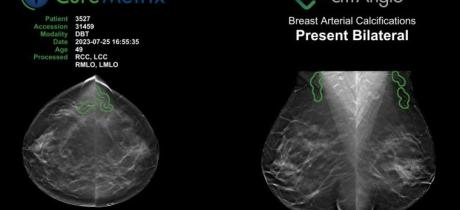

• Two-in-one AI mammogram introduced